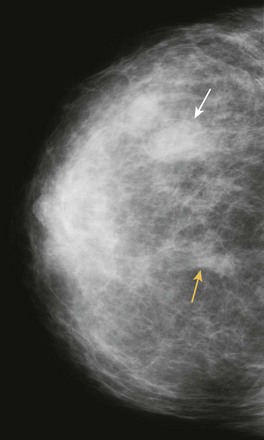

FIGURE 11-15 Parenchymal Angiosarcoma.

This 54-year-old woman developed a new mass (white arrow) in a different location than her prior lumpectomy scar (yellow arrow) from 10 years earlier. Clinically, she presented with a warm, red breast that was suspicious for inflammatory recurrence. (Reprinted with permission from Harvey JA. Unusual breast cancers: Useful clues to expanding the differential diagnosis. Radiology 2007;242:683-694.)